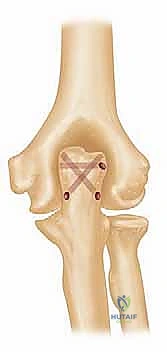

يتم استخدام المفصل الصناعي النهائي، والذي يتكون غالباً من سبيكة معدنية عالية الجودة (مثل الكوبالت والكروم أو التيتانيوم) مع بطانة من البولي إيثيلين لضمان حركة سلسة. يتم تثبيت جذوع المفصل داخل العظام باستخدام "الإسمنت العظمي الطبي" (Bone Cement) الذي يضمن ثباتاً فورياً وقوياً، وهو أمر حاسم لمرضى هشاشة العظام.

6. ربط المفصل وإغلاق الجرح

بعد جفاف الإسمنت، يتم ربط جزئي المفصل (العضد والزند) معاً بمحور معدني (Linked Prosthesis)، مما يمنع خلع المفصل مستقبلاً. يعيد الدكتور هطيف بناء الأوتار (خاصة وتر العضلة الثلاثية) بدقة متناهية، ثم يتم إغلاق الجرح تجميلياً.